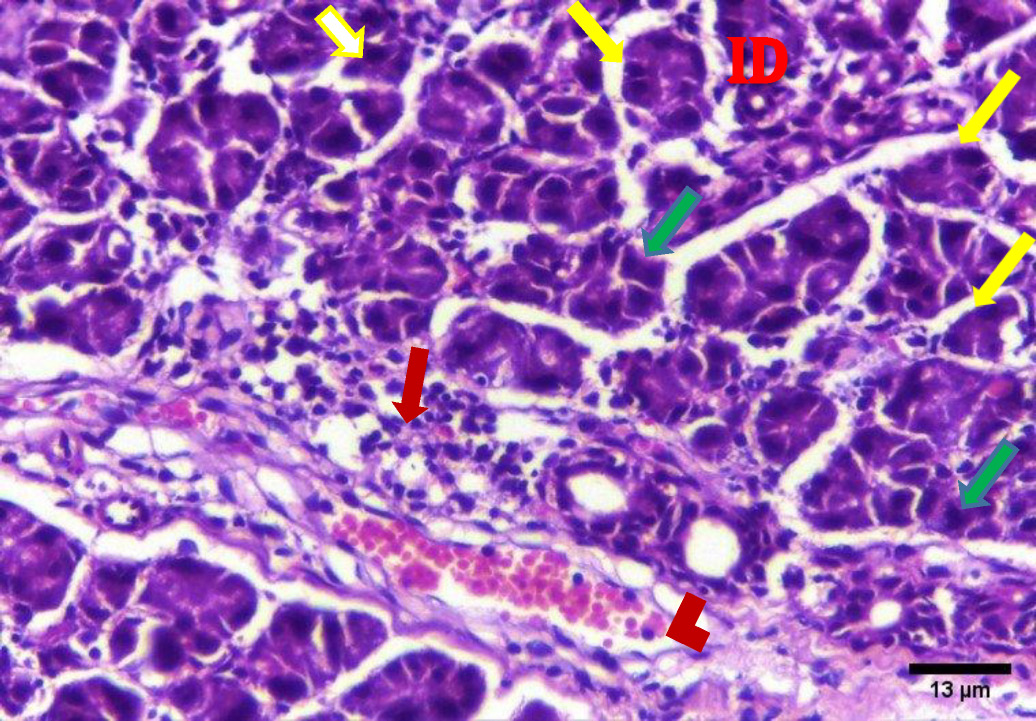

The H&E stained sections of group A (irradiated only) showed degenerative changes at both day 14 and day 30. Acinar shrinkage, multiple cytoplasmic vacuoles and nuclear anisonucleosis and poikilonucleosis were detected. The duct system showed thinning of the epithelial lining of some excretory ducts and stagnant secretion was found in others. Both intercalated and striated ducts showed no detectable changes. Areas of fibrosis were detected in the connective tissue that was chronically infiltrated by inflammatory cells. Additionally, the blood vessels suffered from dilatation and some appeared engorged with RBCs. Also, some blood vessels showed hyalinization and others were ruptured (Figure 2, Figure 3).

The results of the present study showed acinar degeneration, shrinkage and cytoplasmic vacuolization in group A (day 14 and day 30). Boraks, Tampelini, Pereira, and Chopard have linked acinar degeneration and vacuolization to the expansion of the endoplasmic reticulum which is associated with the cellular status that precedes apoptosis this expansion is related to compression of the nuclear material.19

Moreover, the observed nuclear changes (anisonucleosis & poikilonucleosis) and clumped acini with condensed chromatin reported in this work are in agreement with Krishnan et al. who observed shrunken nuclei with condensed chromatin in irradiated salivary gland acinar cells. The author assumed that the irradiation dose was not high enough to cause complete DNA destruction and complete nuclear disintegration.21

In the present investigation, excretory ducts showed degeneration of their lining, others showed stagnant secretion in group A (after 14 days). These findings corroborate with those reported by Kassab, and Tawfik who detected degeneration of excretory duct and stagnant secretion due to oxidative stresses and inflammation in albino rats subjected to long term use of caffeinated drinks.23

In this study, the stagnant secretion found in some excretory ducts in group A was previously shown by Halawa, Mohamed, and Obeid who found some dilated excretory duct with stagnant secretion and concluded that the mitochondrion is the most vulnerable cell organelle to toxic agents and oxidative stresses. Upon mitochondrial destruction in excretory ducts, cellular metabolism was affected with advanced cellular destruction. Destructed mitochondria result in adenosine triphosphate ATP consumption and subsequently, impaired exocytosis took place, so no energy for secretion causing stagnant secretion and ductal dilatation.24

In the current work, connective tissue fibrosis was noted mainly in group A (day 14 and day 30), consistent with Huang, Chen, and Miao who demonstrated that the connective tissue stroma of parotid and submandibular gland of rats undergoes adiposis and fibrosis after irradiation.25

The presence of blood vessels engorged with red blood cells was observed in this investigation in group A (14 and 30 days) which decreased in group B (14 & 30 days). These findings were in agreement with the results of Redman who found thinning and discontinuity in the endothelium lining of blood vessels of the parotid salivary gland of rats that was subjected to irradiation, leading to a compromised blood supply.26

Chronic inflammatory cells infiltration in the connective tissue in this study were clearly observed in group A (day 14 & day 30), replicating findings by Limesand, Said, and Anderson, who found chronic inflammatory cells in response to irradiation of parotid salivary glands of rats.27